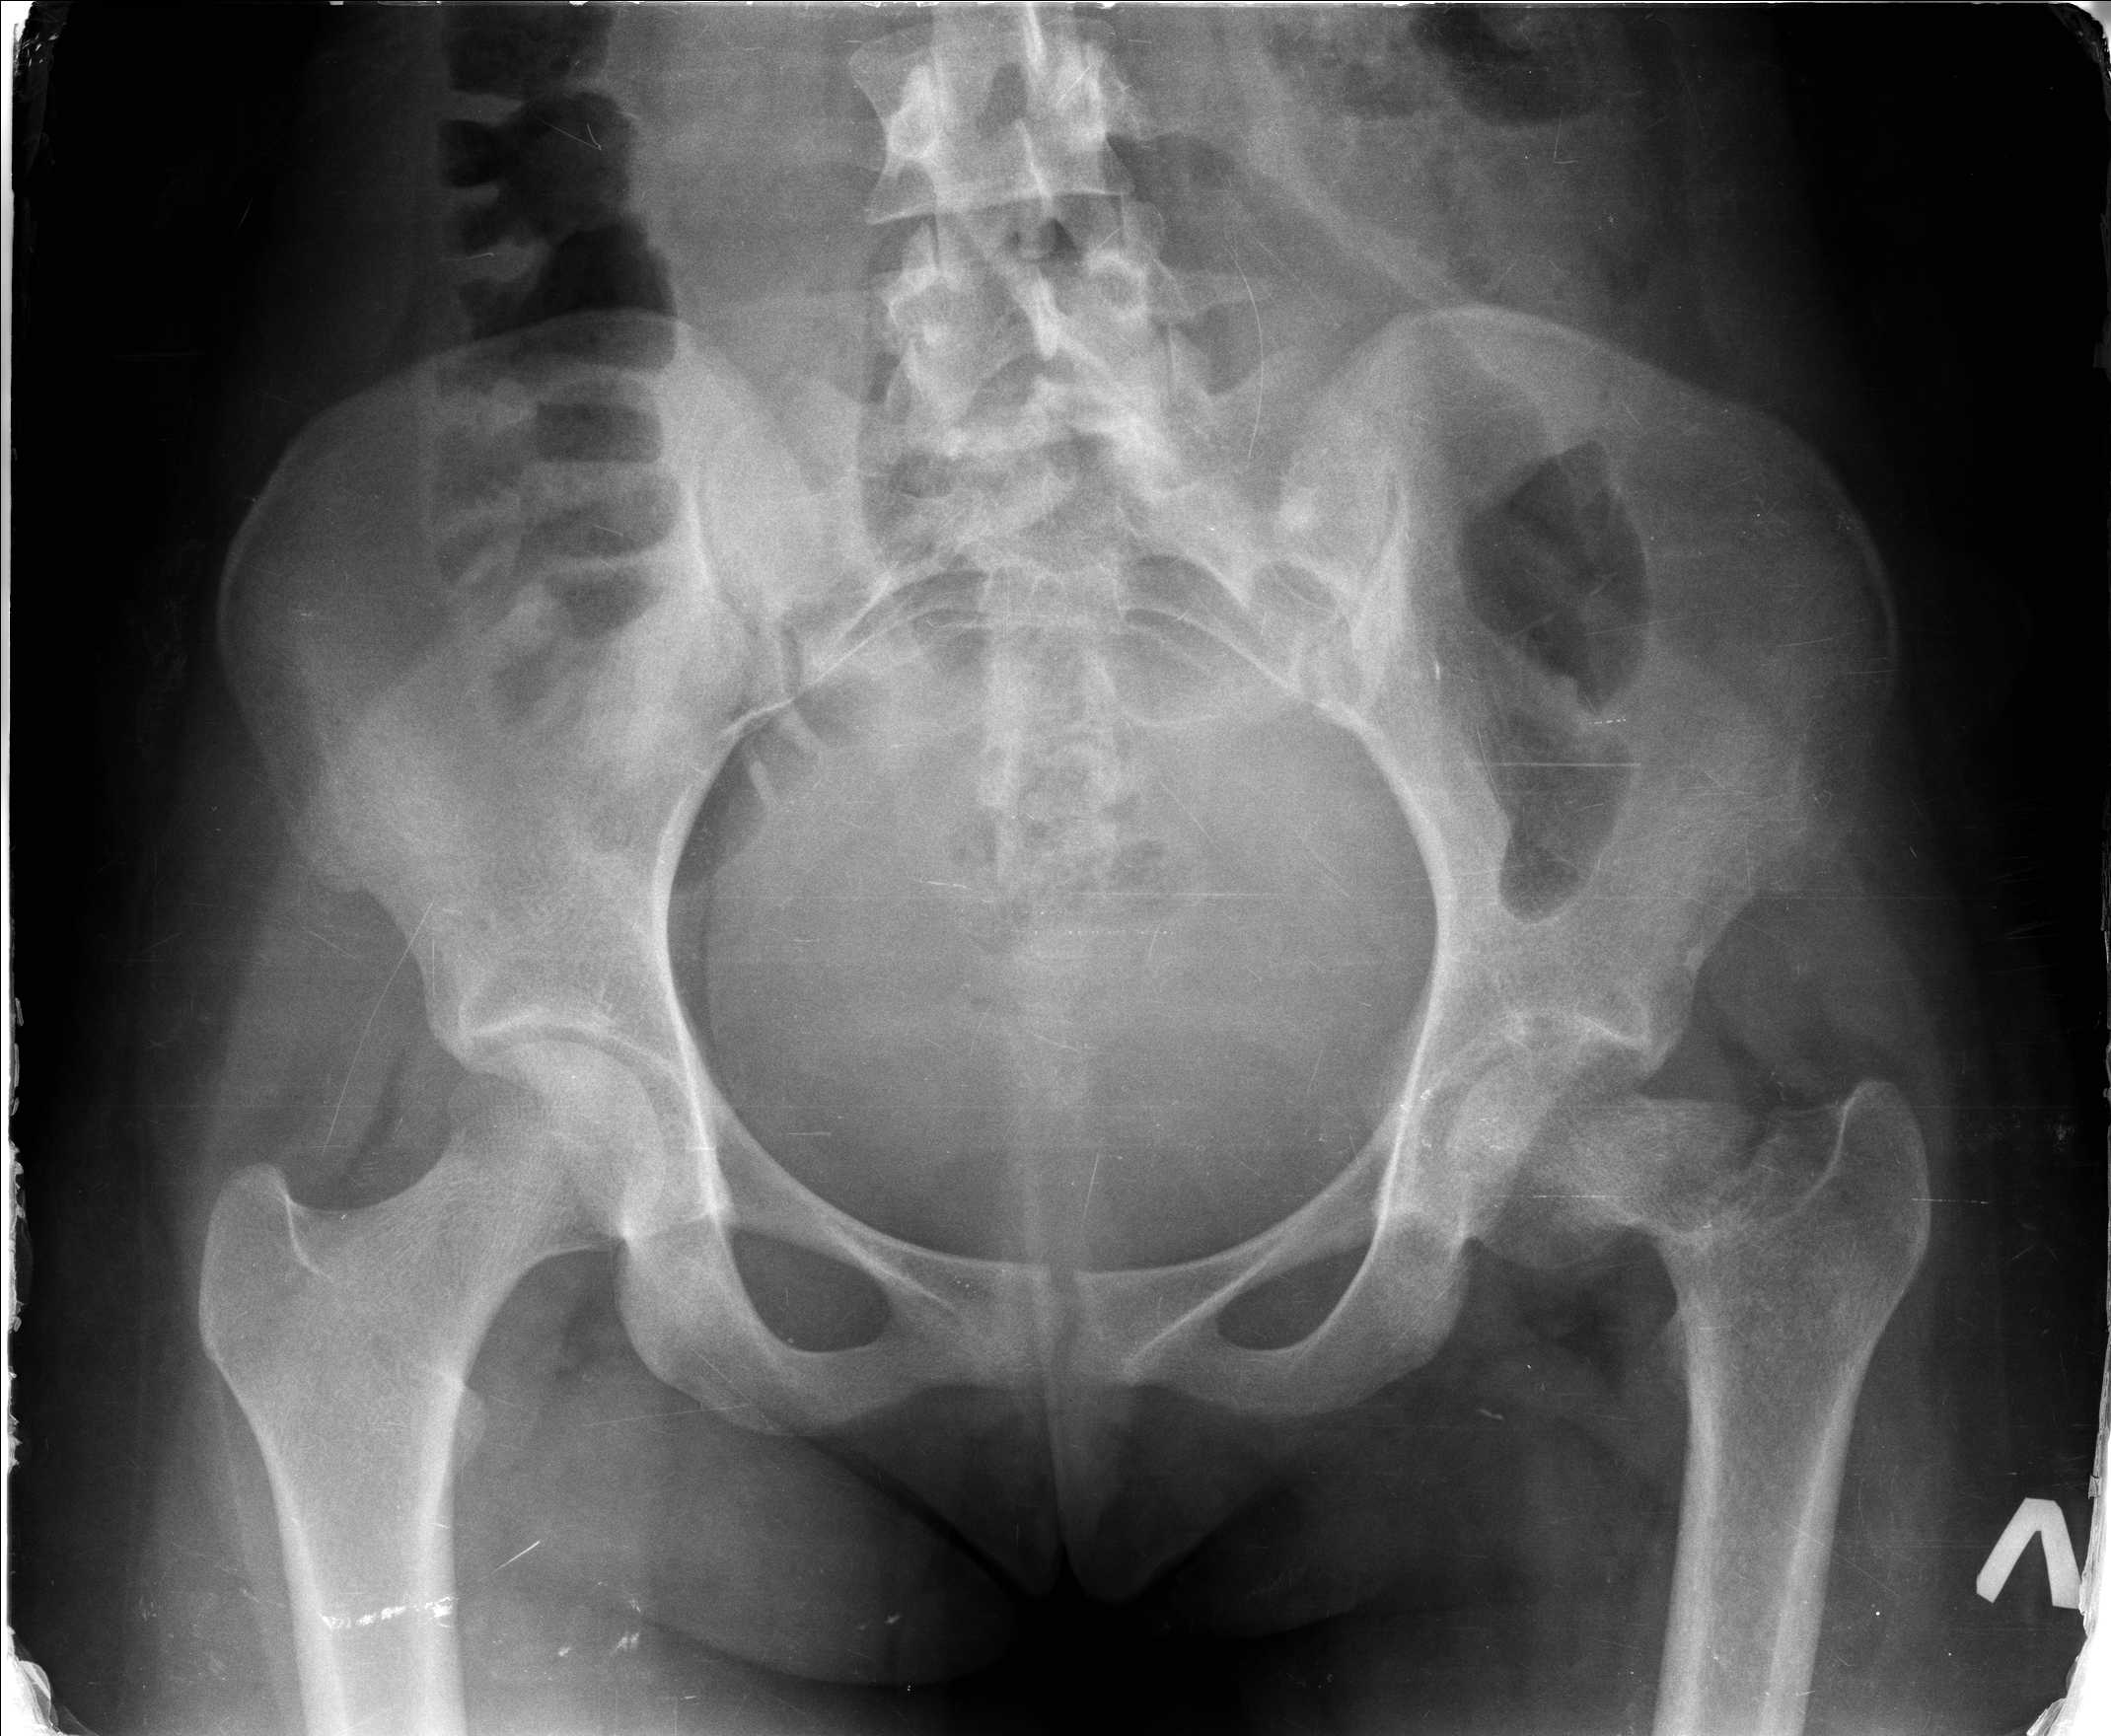

Перелом шейки бедра у девушки 19 лет. Чем лучше помочь?

Добрый день уважаемые коллеги. Во такая ситуация. Девушка 19 лет травму

получила в мае 2016г( изолированная травма, трансцервикальный перелом

шейки левого бедра). Соматически здорова. Лечилась по месту жительства

скелетным вытяжением в течении 1 месяца. Затем переведена в наше

учреждение. 18 июня выполнена операция, детали где , кто и как уточнять

не имеет смысла( из протокола операции: выполнялась передняя артротомия,

репозиция под визуальным контролем) . Учитывая характер выполненного

остеосинтеза, после операции постельный режим 6 недель. Снимки в

хронологии все выкладываю. КТ контроль сделан 2.09.16.  для оценки

состояния  головки бедра. Помогите, определиться с дальнейшей тактикой.